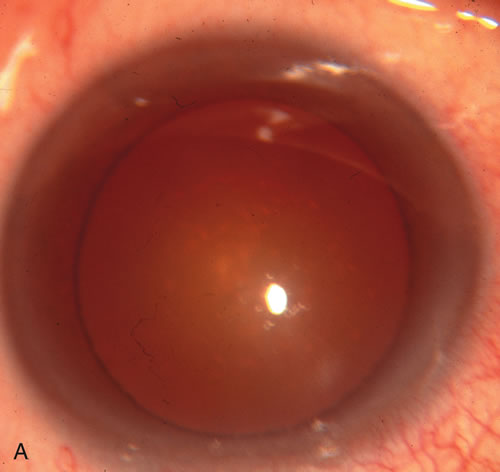

CATARACT EXTRACTION ALONE REDUCES IOP IN MOST EYES WITH ANGLE-CLOSURE GLAUCOMA

Uncomplicated cataract extraction substantially reduces IOP, along with the number of postoperative glaucoma medications in eyes with angle-closure glaucoma.146,147 When preoperative gonioscopy reveals PAS, along with adjacent areas of appositional closure, lens extraction alone in select cases may be a reasonable alternative to filtration surgery.148,149 Phacomorphic angle-closure disease due to enlargement of the lens with progressive angle crowding is eliminated following lens extraction. The width and depth of the anterior chamber angle in eyes with angle-closure glaucoma increases significantly after cataract extraction with IOL implantation and becomes similar to open-angle glaucoma and normal eyes.150,151 (Fig. 5). Combining phacoemulsification, IOL implantation, and limited goniosynechialysis is effective in the treatment of cataract and chronic angle-closure glaucoma.152 Phacoemulsification with implantation of a foldable IOL is more effective in reducing IOP and improving visual acuity than surgical peripheral iridectomy in eyes with acute angle-closure glaucoma.153

Fig. 5. Anterior chamber angle changes associated with lens extraction and PCIOL This 65-year-old Vietnamese woman has a long-standing history of chronic angle-closure glaucoma treated with laser peripheral iridectomy. The optic nerve demonstrated mild glaucomatous damage and IOP was moderately controlled on two antiglaucoma medications. The cataract was removed through temporal clear corneal phacoemulsification with foldable acrylic IOL. A. Symptomatic cataract in narrow-angle glaucoma eye with patent iridectomy. B. Intraoperative goniophotograph showing crowding of angle with increasing narrowness due to phacomorphic component. C. Intraoperative photograph showing temporal clear corneal approach with IOL in the capsular bag. D. Intraoperative goniophotograph demonstrating deepening of chamber angle following lens extraction. Proposed theories for IOP reduction following lens extraction with complete wound closure: